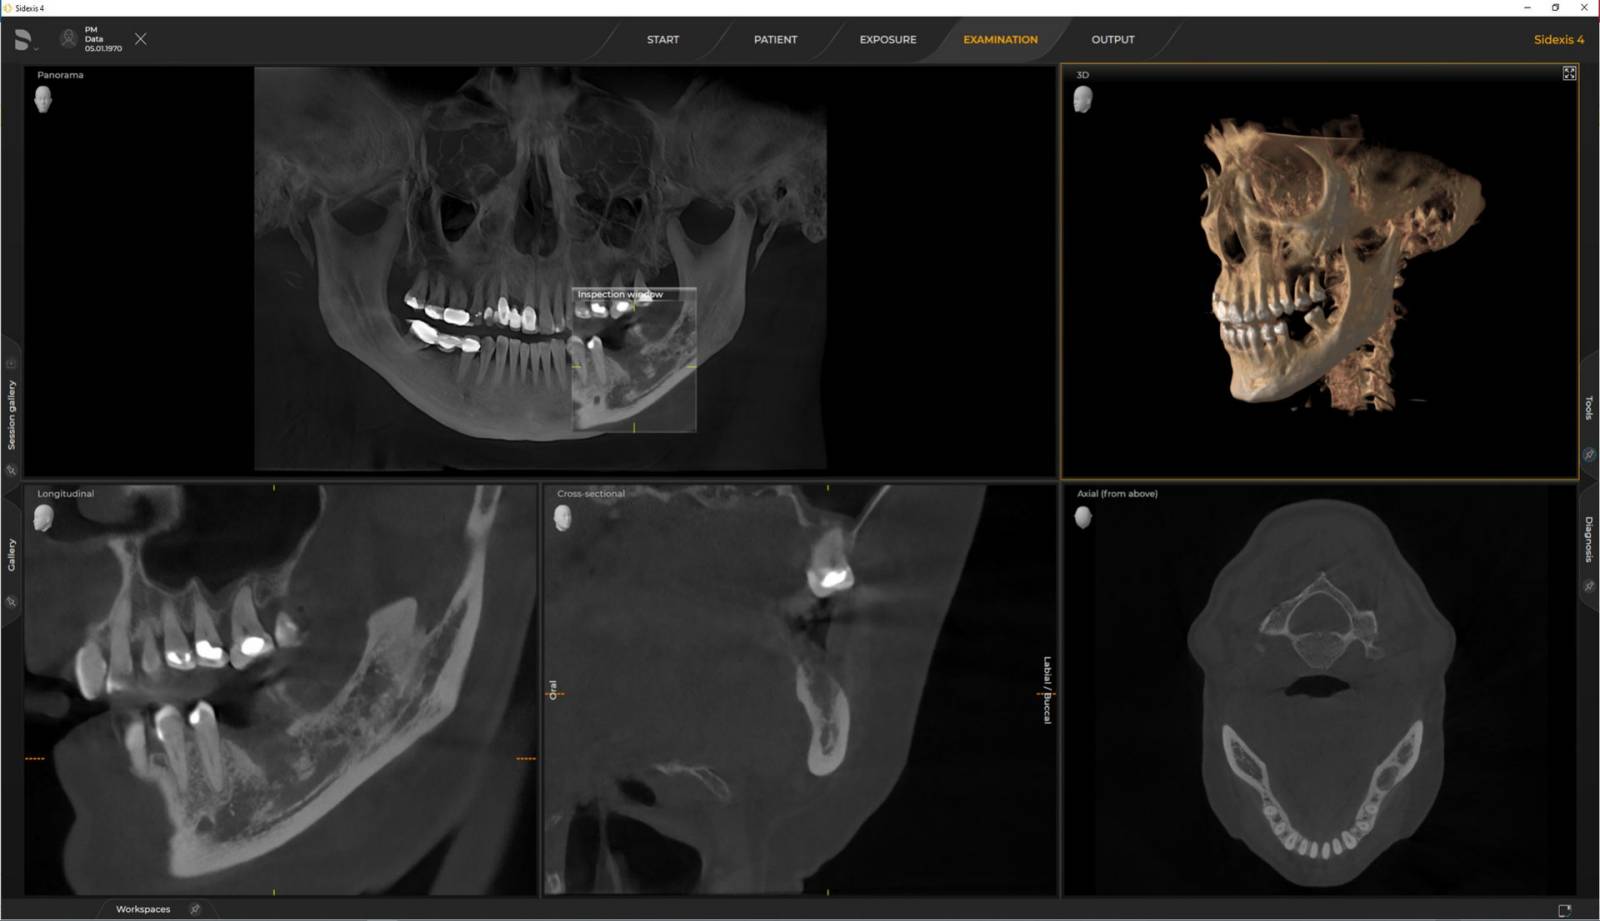

Axeos – the 2D/3D specialist system with a large volume and high image quality for practices with a broad treatment offering. Developed together with dentists and clinicians, Axeos provides the fullest range of functions out of all Dentsply Sirona extraoral X-ray devices. In addition to excellent image quality and tailor-made 3D volume sizes, the dental imaging device is fully optimised for enhanced patient comfort. Axeos not only provides quality in performance and comfort, but also with its award-winning design thanks to the integrated bite block accessory cabinet and ambient light.

Numerous volume sizes ensure flexibility in everyday practice. Examine a precise area or evaluate the complete dentition including the TMJs

Dentsply Sirona 3D units work exclusively with Sidexis 4. Nevertheless data migration from Sidexis XG to Sidexis 4 is very easy. Sidexis 4 allows for the full digital experience with the latest tools.